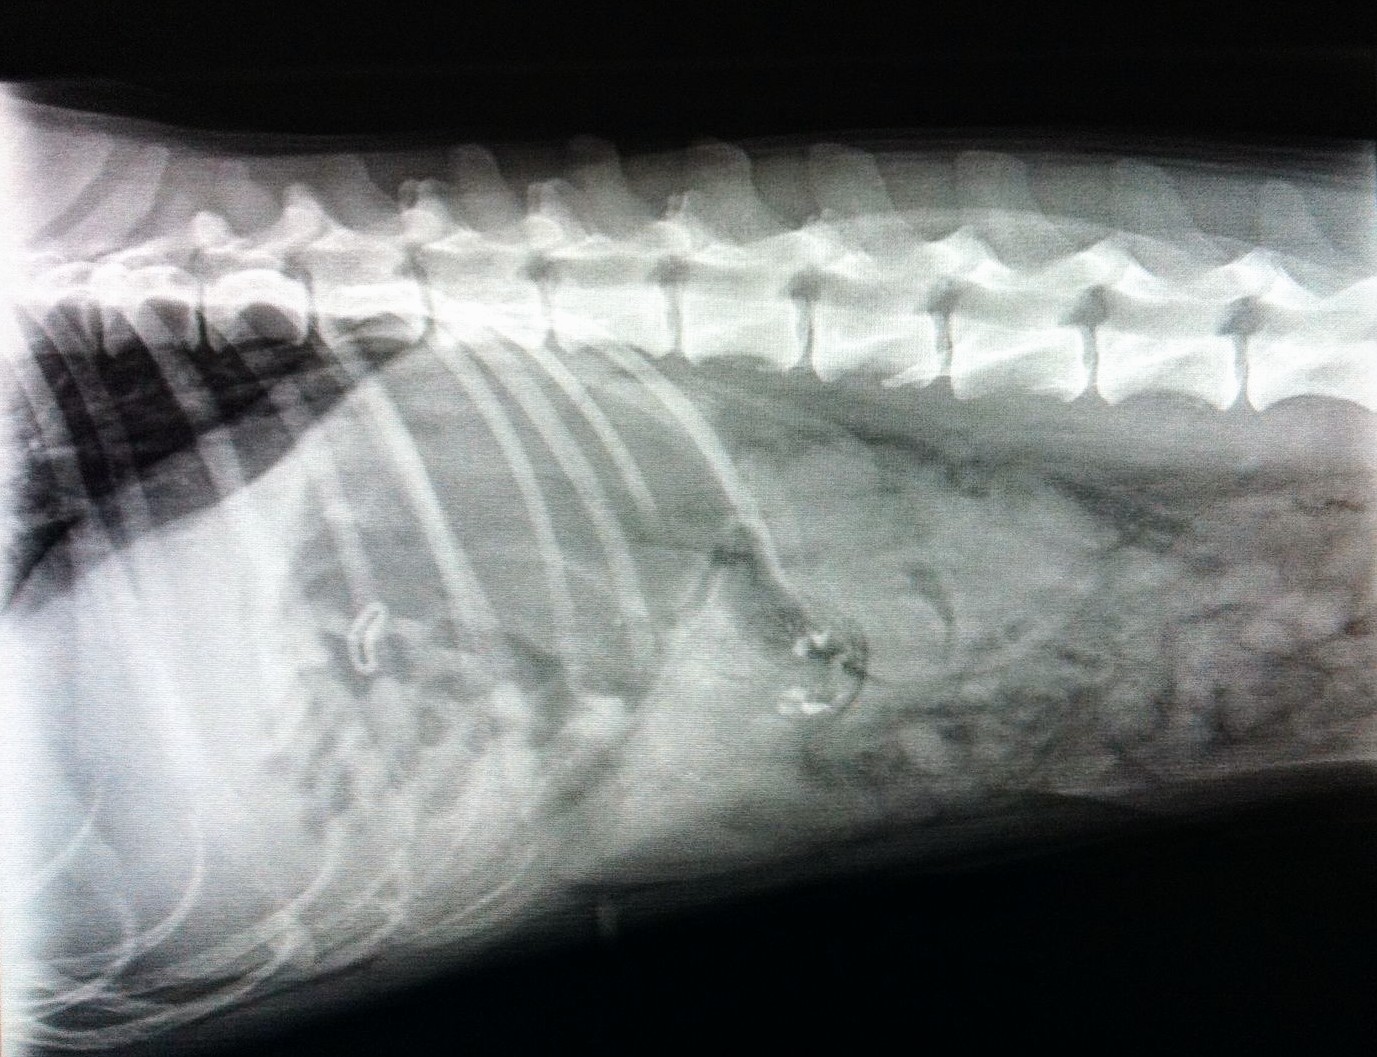

Sie wurde mit einer Schwäche der Hintergliedmaßen vom Haustierarzt ans Kleintierzentrum überwiesen. Nach Röntgen und Ultraschall stand fest, das die Schwäche nur sekundär zu einem Fremdkörper im Bauch des Hundes vorlag. Dieser war bereits vom Magen in den Dünndarm gewandert und verursachte einen Ileus (lebensbedrohlichen Darmverschluss). Aura's Blutwerte zeigten bereits einen massiven Flüssigkeitsverlust und erhöhte Entzündungszellen an, sodass es sich hier nicht um ein orthopädisches, sondern ein chirurgisches Problem handelte und sofort operiert werden musste.